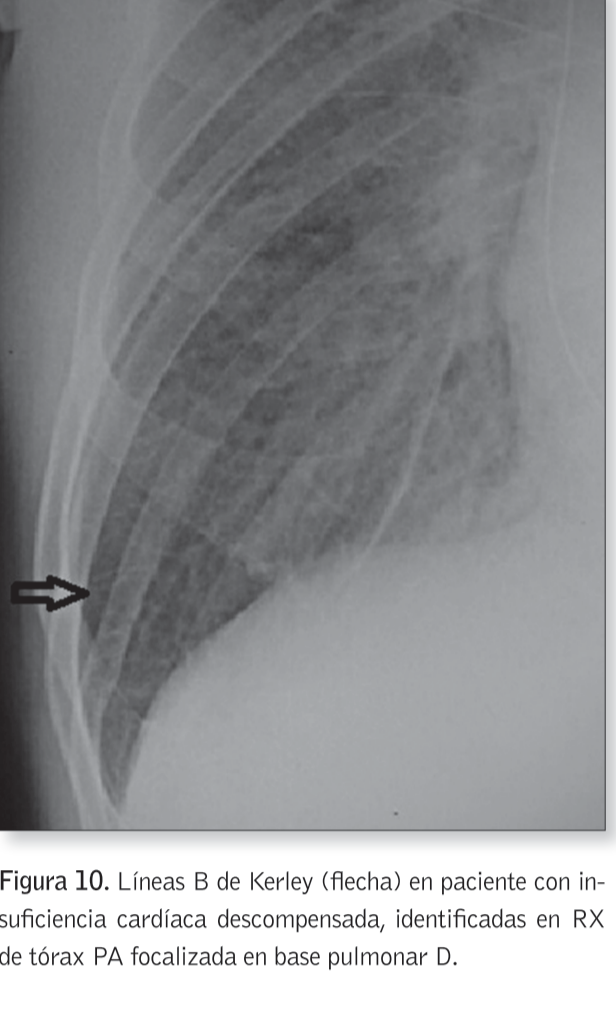

1) Patrón lineal (engrosamiento de septos interlobulillares)

¿Cuándo se presenta el patrón lineal?

Laringitis carcinoma toda

Edema pulmonar